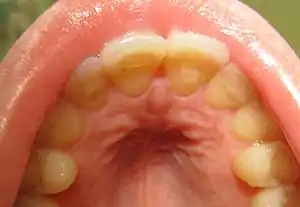

Loss of enamel (acid erosion) from the inside of the upper front teeth as a result of bulimia

People with bulimia are more likely than people without bulimia to have an affective disorder, such as depression or general anxiety disorder. One study found 70% had depression at some time in their lives (as opposed to 26% for adult females in the general population), rising to 88% for all affective disorders combined.[25] Another study by the Royal Children's Hospital in Melbourne on a cohort of 2,000 adolescents similarly found that those meeting at least two of the DSM-IV criteria for bulimia nervosa or anorexia nervosa had a sixfold increase in risk of anxiety and a doubled risk for substance dependency.[26] Some with anorexia nervosa exhibit episodes of bulimic tendencies through purging (either through self-induced vomiting or laxatives) as a way to quickly remove food in their system.[27] There may be an increased risk for diabetes mellitus type 2.[28] Bulimia also has negative effects on a person's teeth due to the acid passed through the mouth from frequent vomiting causing acid erosion, mainly on the posterior dental surface.